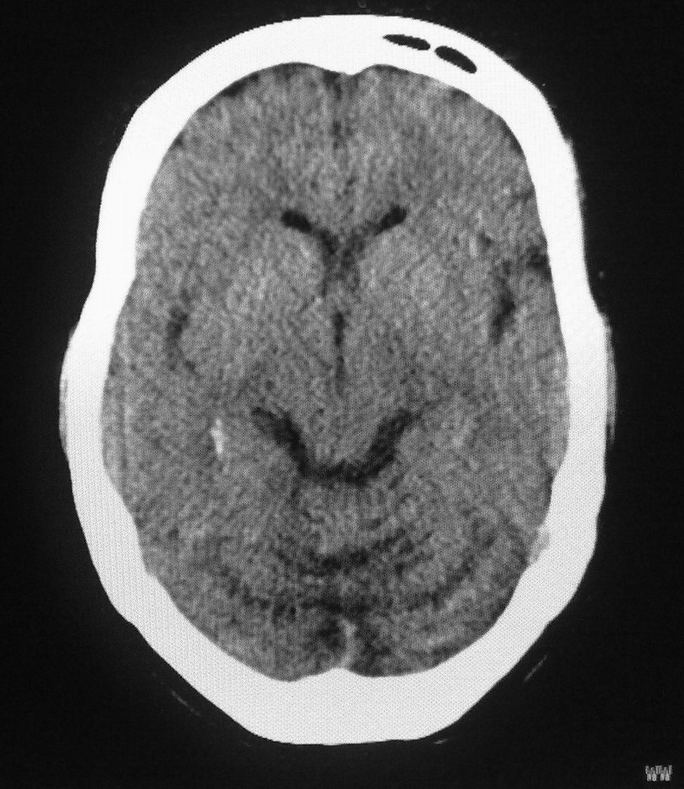

女,46岁,走路有时向一侧偏斜。是小脑萎缩吗?

小脑脑沟增多加深      为小脑萎缩引起的共济失调

小脑脑沟多于四条即为增多,又见加深,所以支持小脑萎缩。

从图像上看的确有轻度小脑萎缩征象,但患者才46岁,有外伤史吗?

小脑萎缩可能性大,建议mri检查。

小脑轻度萎缩